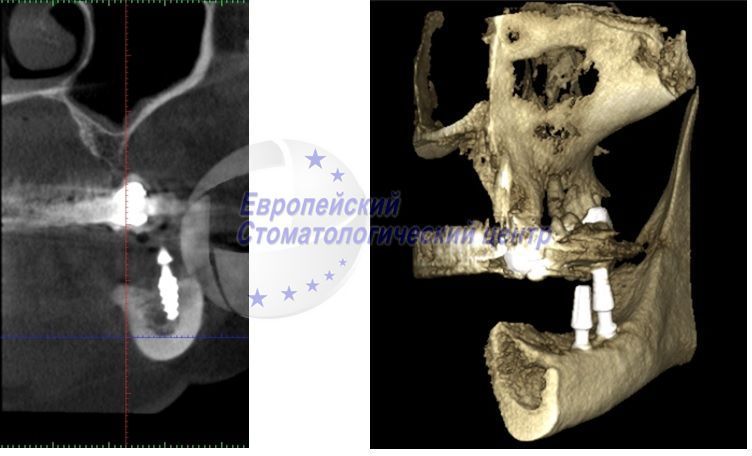

кт після операції

КТ після операції імплантати стоять поруч з нижньощелепним каналом